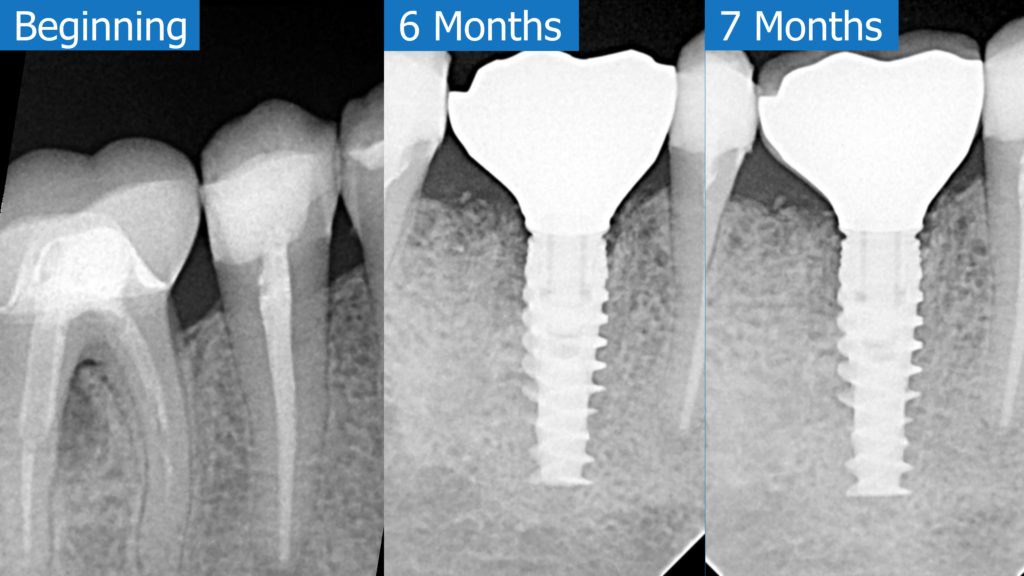

A healthy 36 year old woman comes to the clinic with pain and swelling in the area of the inferior left molars. In the intraoral observation, a vestibular fistula was identified, and the complementary exams confirmed a bone lesion caused by a root perforation (poorly executed false post) on the first lower left molar #36 (19). It was decided to do antibiotic therapy for a week and then the tooth extraction with immediate implant placement and bone graft. 4 months post-op the definitive zirconia/ceramic crown would be was made.